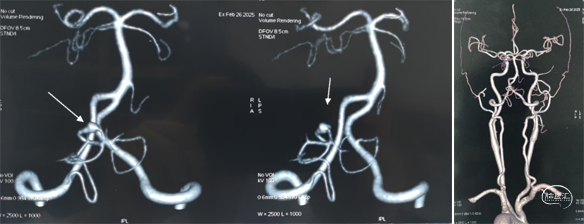

颅脑MRI+MRA

术前DSA

<<左右滑动 查看更多>>